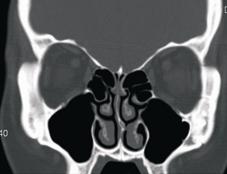

需接受手術的病患,在手術前均需接受電腦斷層掃描的詳細檢查,正常的鼻竇在影像上應為黑色的空腔(圖二),鼻竇炎手術的最新進展 「電磁式鼻竇導航手術」(相關圖片)若被發炎組織所堵塞,則呈現灰白色顯影,即為發炎感染的範圍(圖三),鼻竇炎手術的最新進展 「電磁式鼻竇導航手術」(相關圖片)也就是手術醫師要以手術器械清除的部份。一般而言,進行這樣的手術需要住院,在全身麻醉下進行,以利醫師將病灶部位徹底清除,才不會復發。